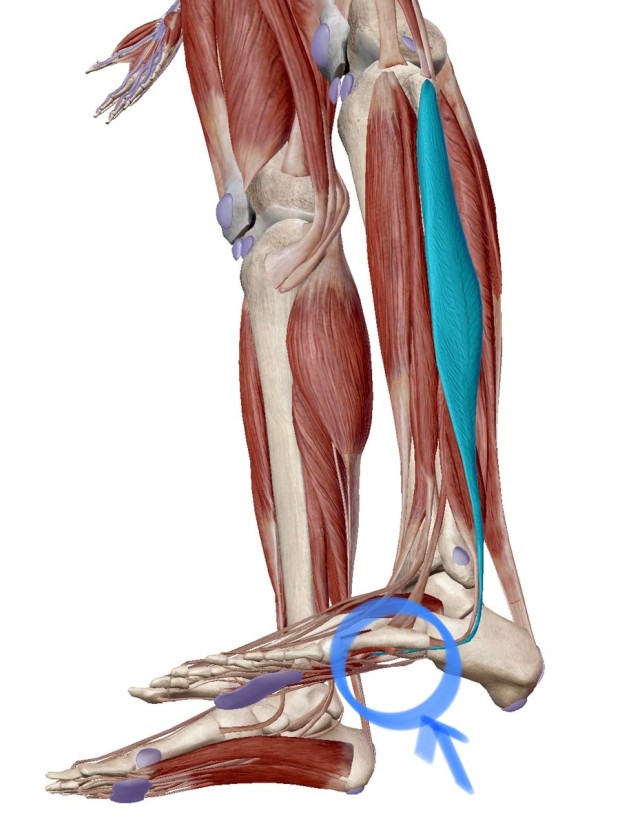

족저 근막염은 발바닥에 위치한 족저근막에 염증이 생기는 질환으로, 발꿈치에 통증을 유발합니다. 주로 하루 중 첫 번째 걸음에서 통증이 심하게 나타나며, 장기간 서 있거나 걷는 것에 어려움을 겪을 수 있습니다. 과도한 운동이나 비만, 잘못된 신발 착용 등으로 발병할 수 있습니다.

족저 근막염의 치료에서 중요한 것은 발바닥과 종아리 근육 스트레칭입니다. 발꿈치 근육을 풀어주는 스트레칭을 꾸준히 하면 통증 완화에 도움이 됩니다.